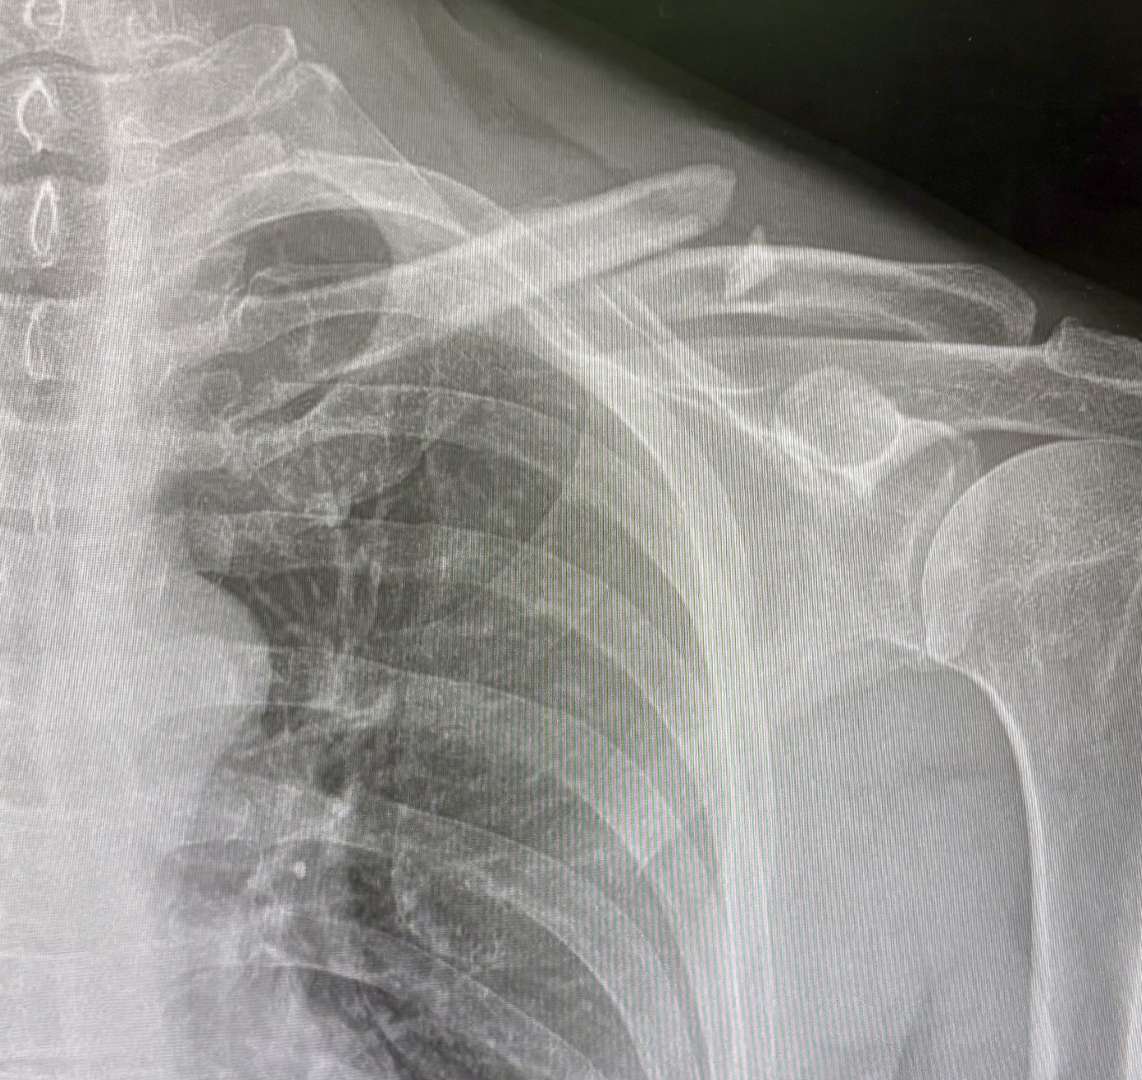

I’ll add some photos - personally I’m glad I got it plated at this moment in time as everything was moving about prior to having it plated and any kind of transport (bus / car) was jarring it. Immediately after plating this became instantly more comfortable.

That's quite a gap! I can see why you had it plated. Mine never hurt amazingly until the AC joined the party. It did grind a bit for the first week but then stablilised. That image is when I did it and about 7 weeks in where you can see new bone but it's very gray (soft).

Things are progressing steadily - the fracture is gradually filling in on the x rays - but you can still clearly see where it was broken at last x ray (the black line is gradually going mistier on the x ray). I’m now using light stretchy bands to start building up strength in the shoulder after spending a while working on getting a better range of motion in it (all based on instructions from the consultant and a physio).

Mine was May 26. You can see in that thread it was quite a separation. After 12 weeks new bone growth has joined the two halves and consultant said it's as strong or stronger than before. A friend did his the week after and had his plated. He still has a small fragment not attaching so he's been told to leave it another three months before (hopefully) the x-ray will show it fully healed.